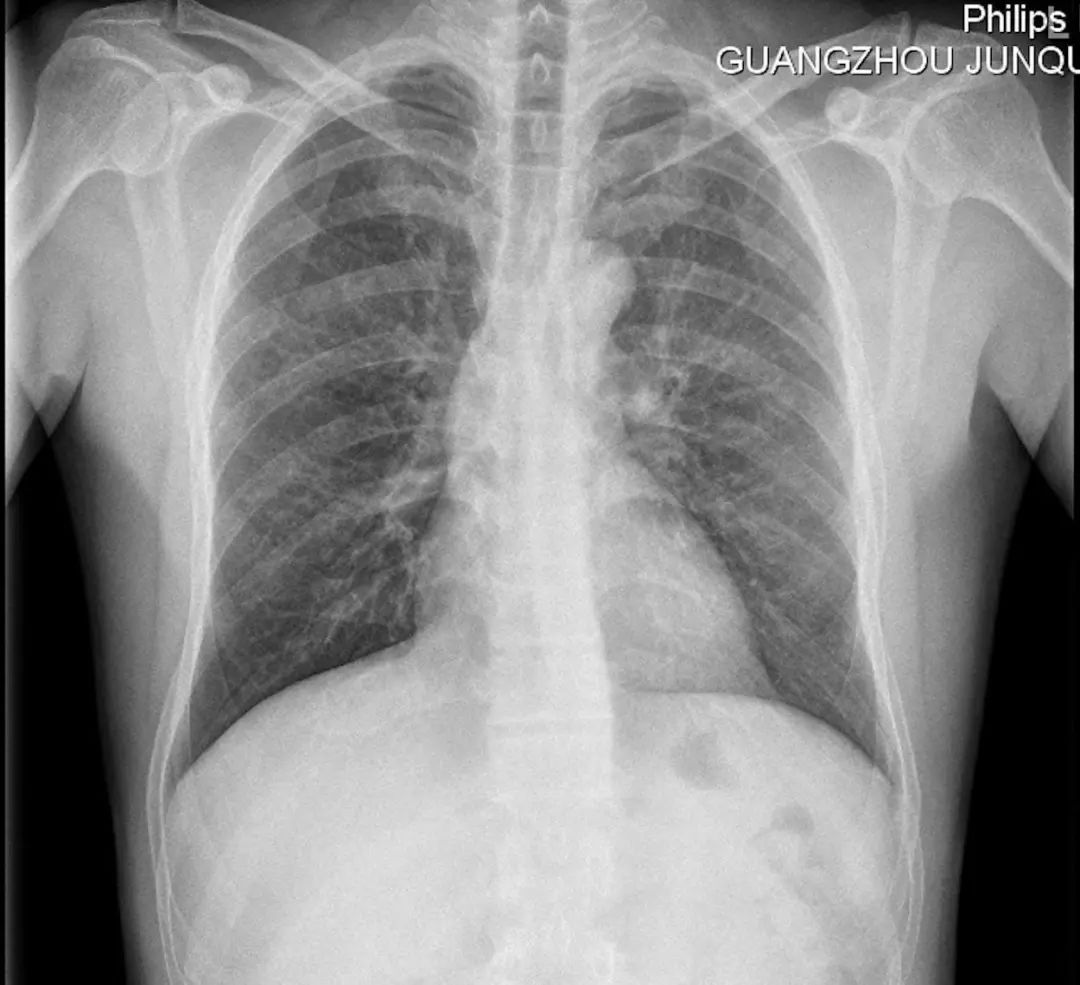

出现严重肺部感染后,我首先回顾了术前的胸片,也没有发现严重的问题?!